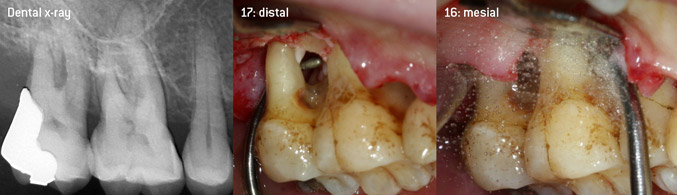

Débridement ouvert des furcations sur les dents 16 et 17

Figure 3 : Débridement ouvert des furcations sur les dents 16 et 17 en cas de perte d'attache avancée

L'objectif était de développer un insert universellement applicable afin d'éviter les changements d'insert qui prennent du temps. En outre, il devrait être plus facile d'utiliser les nouveaux inserts dans les poches intra-osseuses étroites à partir de l'entrée distale et à l'entrée distale de la furcation des molaires maxillaires, ce qui permettrait une utilisation plus efficace des instruments. Pour ce faire, une courbe d'instrument de plus grand diamètre a été utilisée (figure 1), ce qui est très avantageux pour le débridement fermé des dents présentant une perte d'attache avancée et une implication de la furcation en particulier (figure 4).